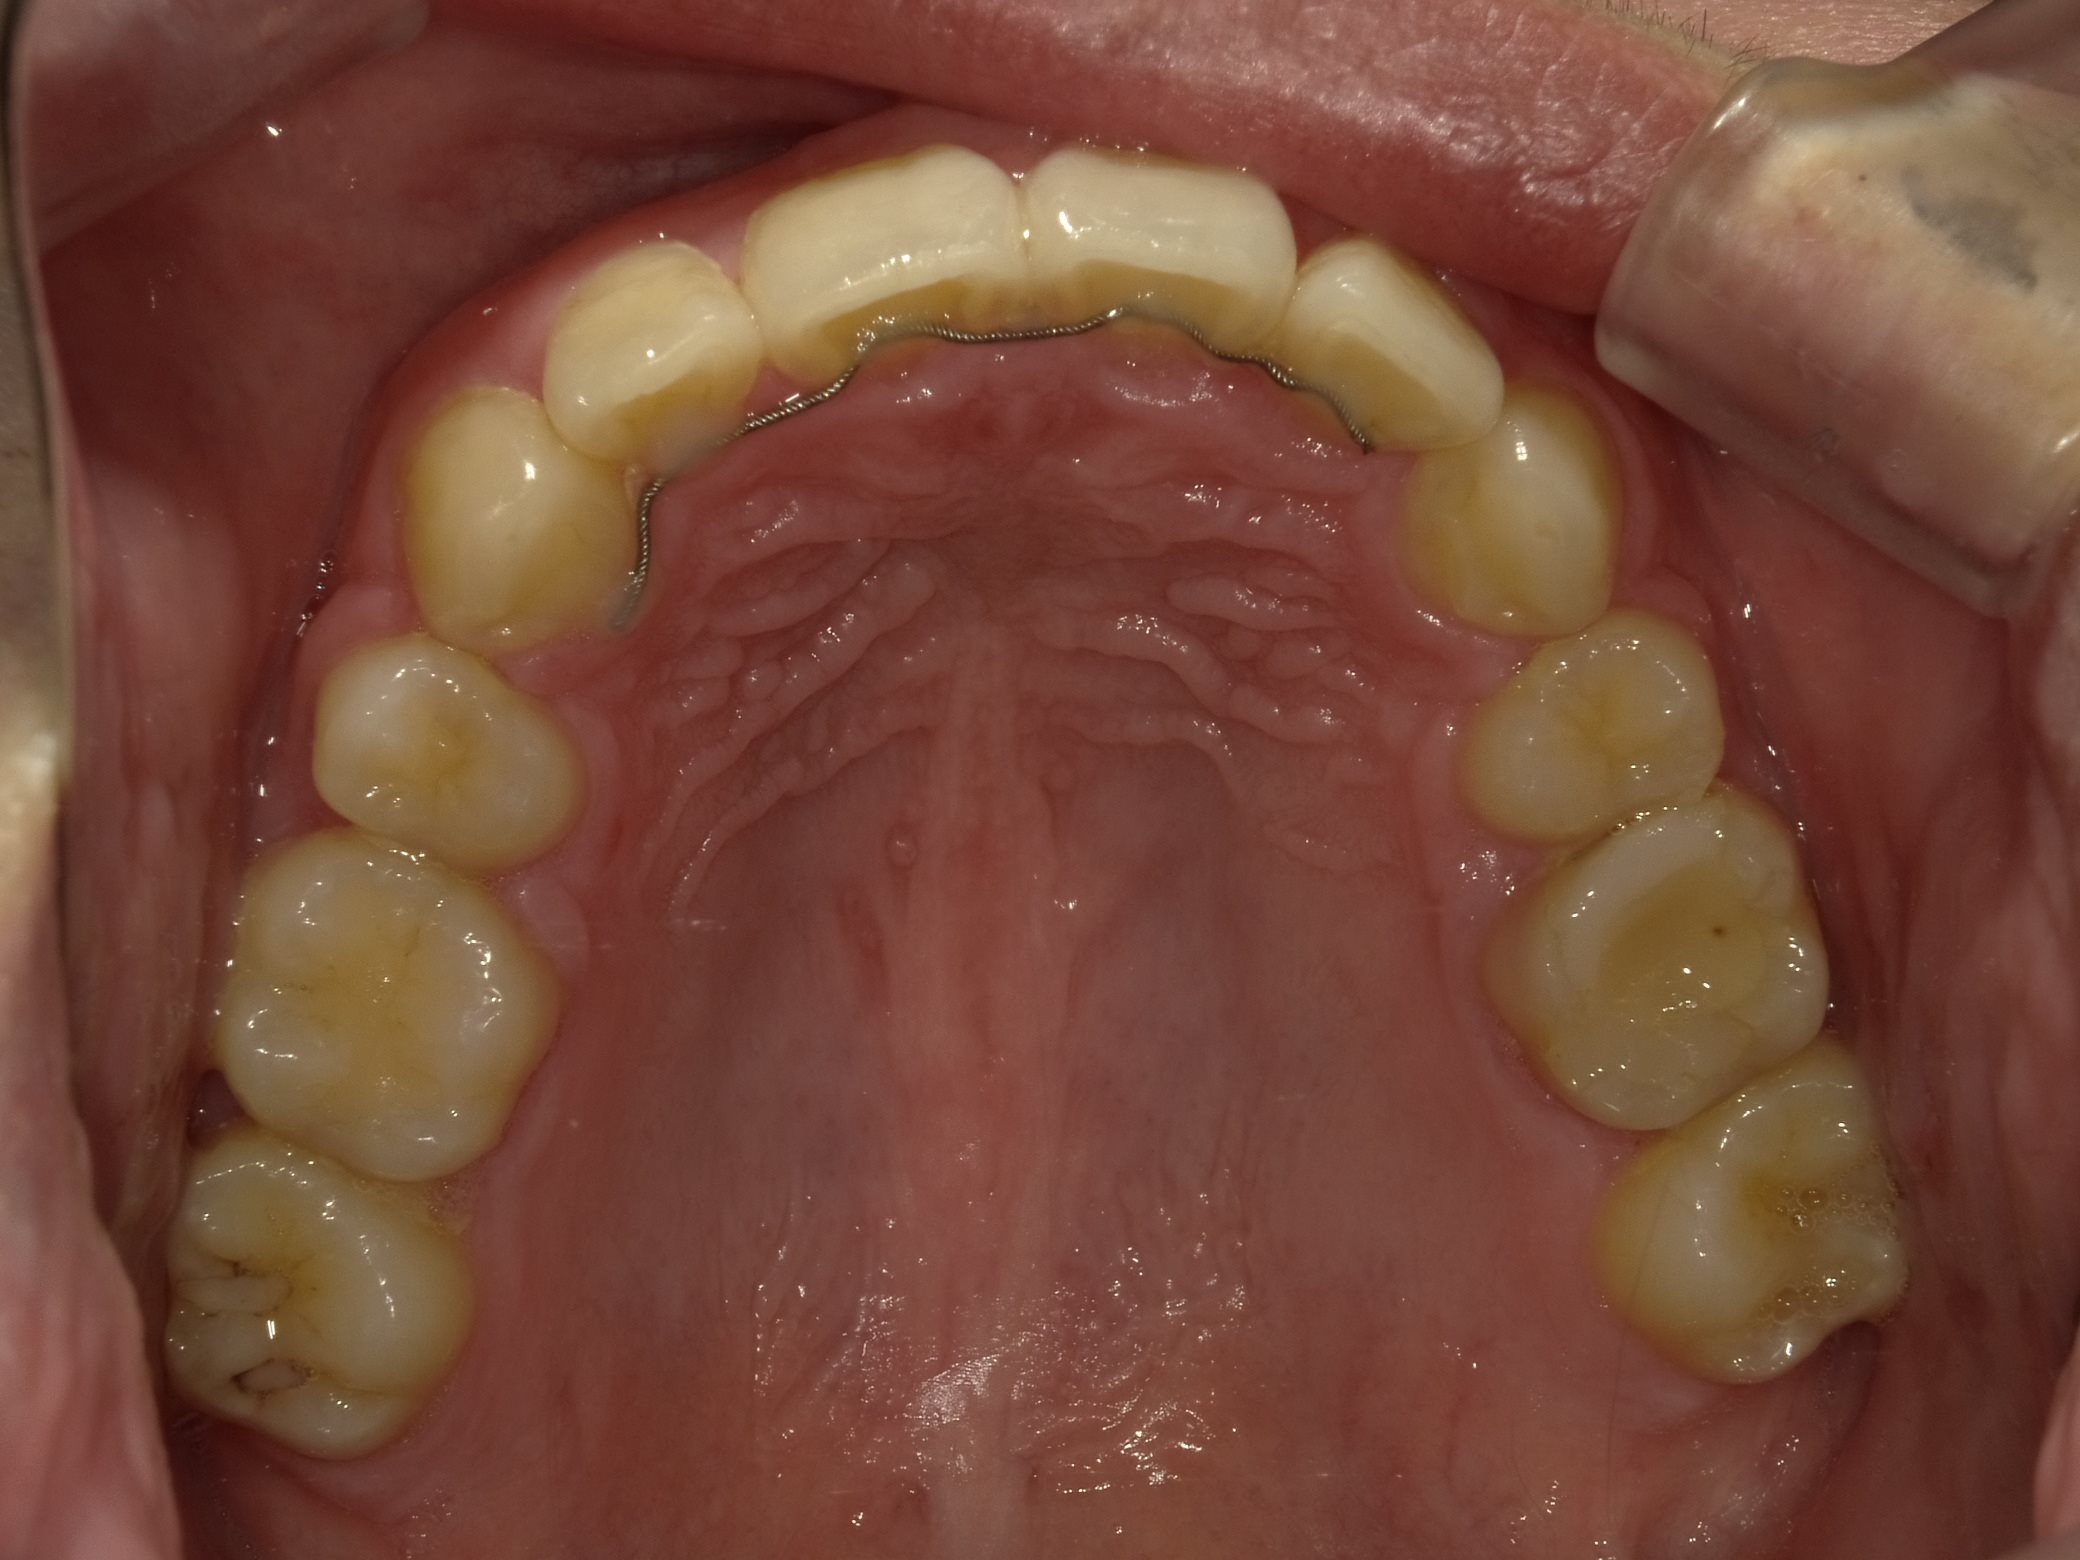

矯正治療が終了しました。

治療前後で比較します。

下の前歯のがたつきもなくなり、上の前歯が内側に入ってきているのが分かると思います。全体的にとてもキレイに仕上がり、大変満足していただけました。